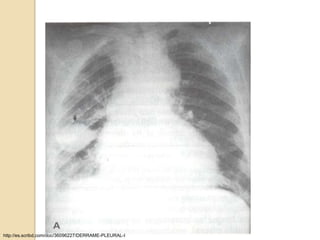

RADIOGRAFIA DE TORAX

 No se puede detectar la etiología del

derrame

 Hallazgos: borramiento del ángulo

costofrénico u opacificación de la base

del hemitórax.

 El líquido forma una concavidad

superior denominada Menisco Pleural.

   Desplazamiento del mediastino hacia el

lado contrario al derrame.

   En las radiografías laterales pueden

identificarse cantidades de líquido a partir

de 25-50 ml, y en las PA a partir de unos

200-300 ml